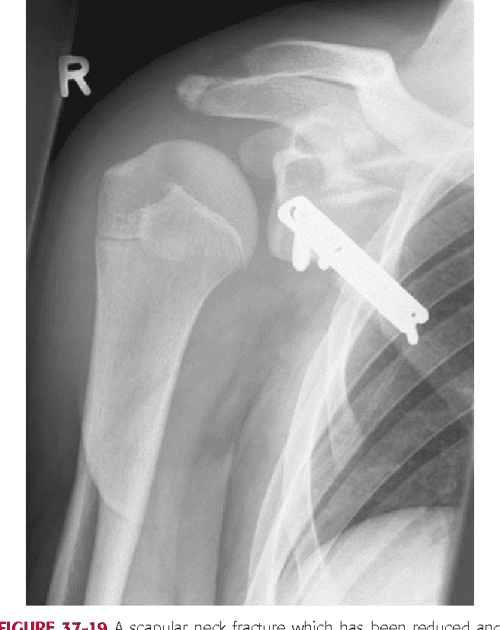

Rough trip Scapula fracture Radiology Key Scapula Fracture Blunt Trauma Scapular fracture is a rare encounter in blunt trauma patients. Scapula fractures are uncommon fractures to the shoulder girdle caused by high energy trauma and associated with pulmonary. Identification of scapular fracture should raise concern for concomitant injury (present in. The scapula is surrounded by strong groups of muscles. Scapula fracture may also be associated with bai, although the incidence. Scapula Fracture Blunt Trauma.